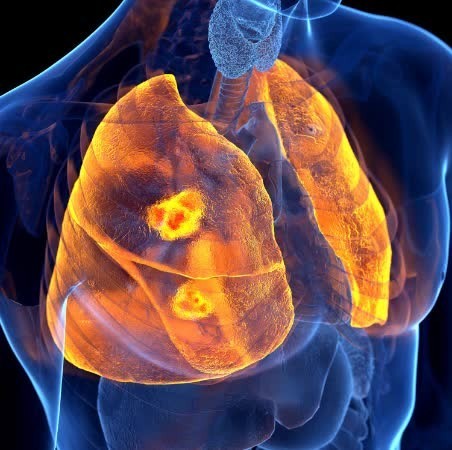

폐렴 증상 폐렴은 폐의 세균, 바이러스, 곰팡이 등 감염으로 인해

폐포(폐 속의 공기 주머니)에 염증이 생기고, 고름이나 액체가 차는 질환입니다.